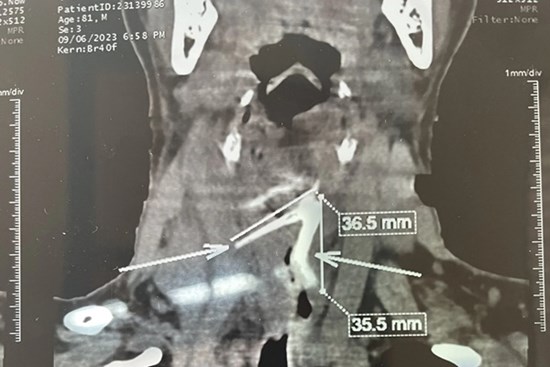

Hóc xương gà, cụ ông bị thủng thực quản suýt chết

Chiếc xương gà sâu trong thực quản khiến cụ ông đau nhức, viêm trung thất và thủng thực quản.​​​​​​​